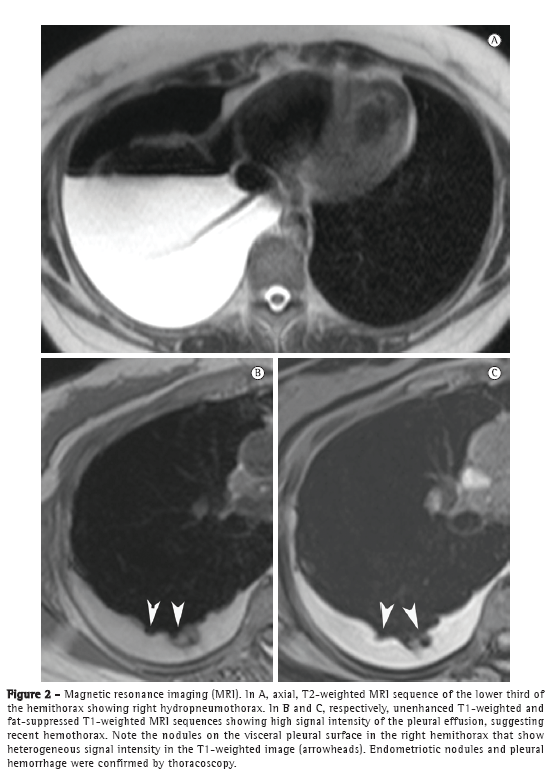

The patient remained asymptomatic for 4 years. Approximately six months prior to this writing, the patient presented with cyclic dyspnea, dry cough, and mild pelvic pain, despite her use of oral contraceptives. A chest X-ray and a CT scan of the chest revealed mild right hydropneumothorax. The lung parenchyma was normal. On T1- and T2-weighted MRI sequences of the chest, performed with and without fat suppression, we observed right hydropneumothorax, and T1-weighted MRI sequences with fat suppression showed hyperintense nodular lesions in the pleura; some of those lesions showed restricted diffusion (Figure 1), which is suggestive of endometriomas.

In recent years, MRI of the chest has progressed markedly. Because of improvements in speed and image quality, MRI is now ready for routine clinical use.(7-9) In both of the cases presented here, chest MRI revealed hydropneumothorax and well-defined, rounded nodules on the pleural surface in the right hemithorax. In Case 1, the pleural effusion had intermediate signal intensity on T1-weighted images, suggesting high protein content, probably related to hemorrhagic products. In Case 2, the pleural effusion had high signal intensity, suggesting recent hemothorax. The pleural nodules observed in Case 1 showed homogeneously high signal intensity on fat-suppressed T1-weighted images and restricted diffusion on diffusion-weighted imaging (DWI). In Case 2, the nodules showed heterogeneous signal intensity on T1- and T2-weighted images, without diffusion restriction. As in pelvic endometriosis,(1,10) pleural nodules of thoracic endometriosis might show different signal intensity on T1- and T2-weighted images, as well as variable diffusion restriction, depending on the age of the lesion.

One of the most rapidly evolving techniques in the MRI field is DWI. This method explores the random diffusional motion of water molecules, which has intriguing properties depending on the physiological and anatomical environment of the organism studied. Although DWI has been applied in the study of pelvic endometriosis, there have as yet been no significant results.(1,10) However, our findings demonstrate that DWI might be useful for the detection of small endometriomas in pleural endometriosis.